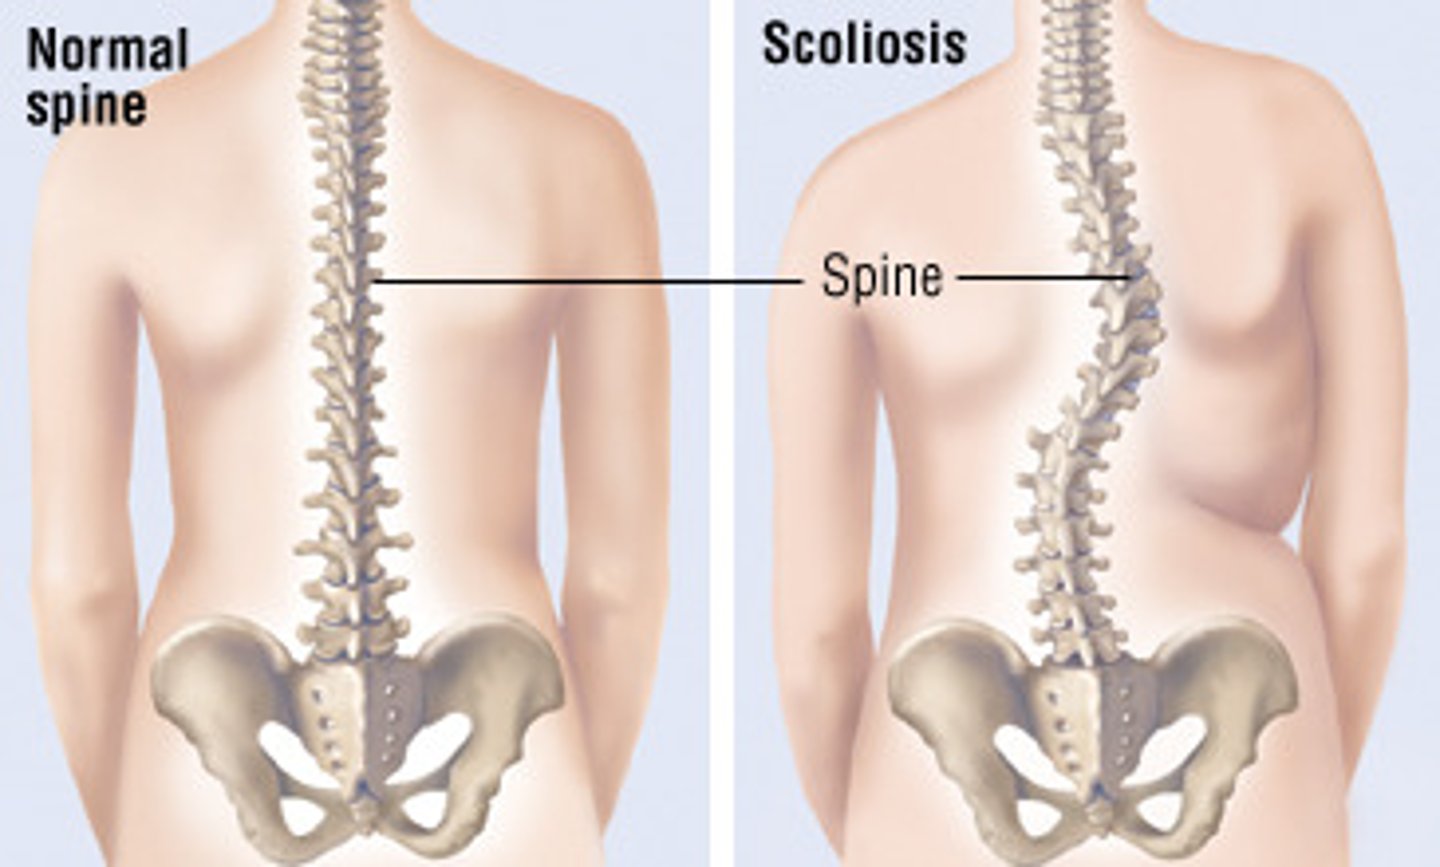

What is scoliosis?

abnormal lateral curvature of the spine